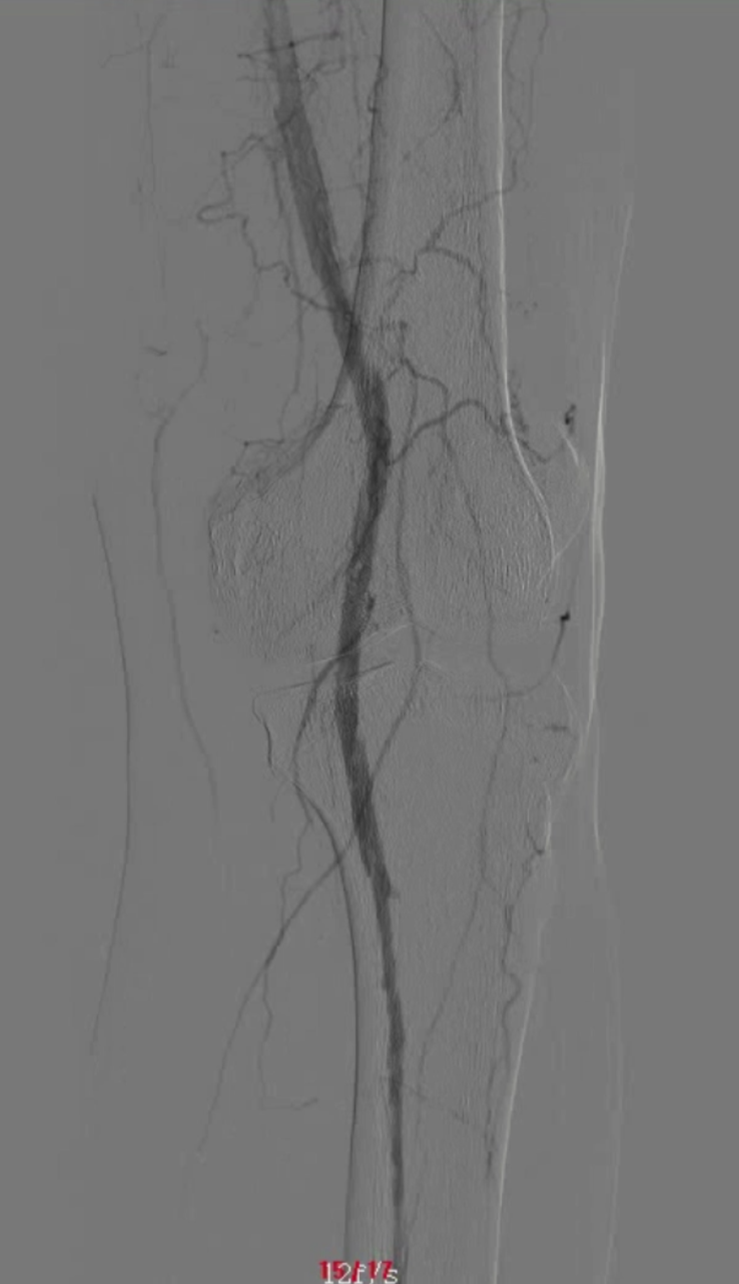

48岁男性,右足溃疡反复发作,多次PTA+DCB治疗

2023.3 右足部溃疡2个月,行PTA

2024.5,再发溃疡4个月,先后两次PTA

2024.9,溃疡未愈合,胫前动脉、胫后动脉PTA+DCB